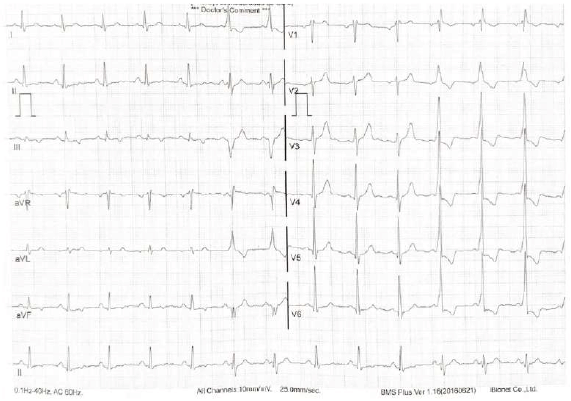

Homem de 38 anos, procedente de Uberlândia-MG, comparece ao consultório do cardiologista com queixa de palpitações recorrentes há 4 meses. Nega comorbidades e apresenta exame físico normal. Realizou o eletrocardiograma reproduzido abaixo.

Sobre o caso, o especialista conclui que